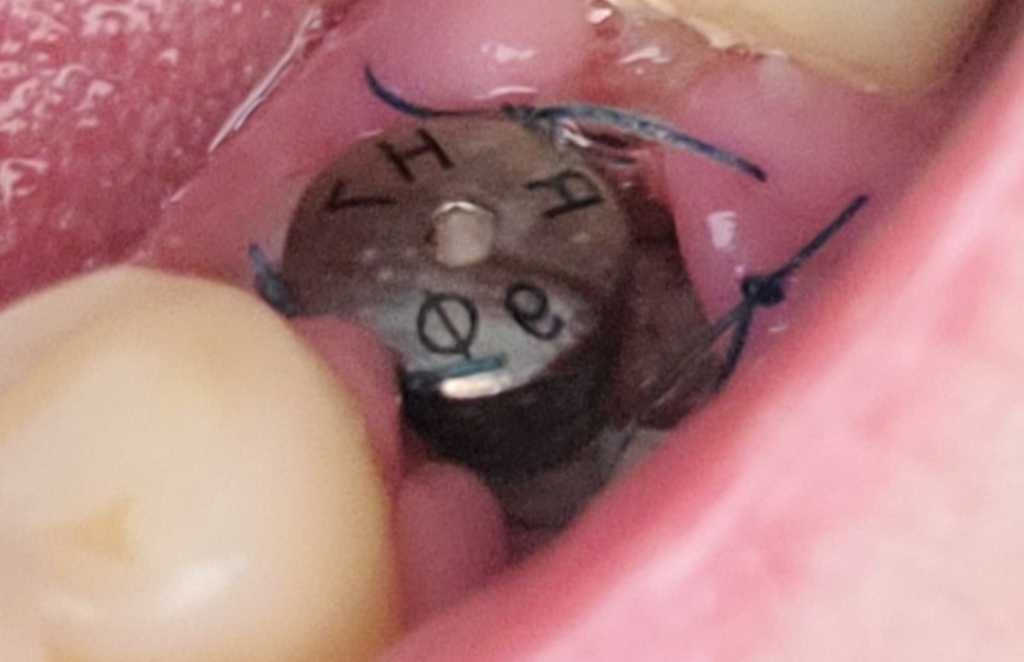

발치후 임플란트 식립 5일 되었는데 나사 주위에 잇몸이 많이 꺼져있어요..하얀물질도 보이고 괜찮은건가요?

아님 재수술해야하나요?

• 1번 째 사진

잇몸이 내려간게 아닙니다. 수술하는 과정중에 잇몸을 열엇기 때문에 그런거며, 아직 수술하신지 얼마 안되신거 같은데 잇몸이 다 아문상태가 아니라서 그런거니 너무 걱정하지 않으셔도 됩니다.

통증이나 불편감이 없나요? 통증이나 불편감이 없다면 정상적인 섬유화과정이 동반되고 있다고 보여지기는 하나 잇몸이 정상적으로 차오르지 않고 있기 때문에 치과를 한 번 방문하는 것이 좋을 수 있습니다. 이는 치료가 잘못되었다기 보다는 어떠한 방향으로 식립했는지에 따라 다를 수 있으므로 해당 시술을 하신 선생님에게 물어보는 것이 가장 좋습니다.

임플란트를 수술하고난뒤에 잇몸이 안정적으로 아무는데는 2주정도 의 시간이 걸립니다.

아질 5일밖에 되지 않은것이라면 잇몸에 덜 아무는 시기 이기 때문에 해당부위를 자극하지 않도록 하는것이 좋습니다 .

하얀 물질은 보통 상피세포가 회복되면서 생기는 것이지만 상태를 보았을 때 치과를 한번 내원해보시는 게 좋겠습니다.

하얀색은 잇몸이 치유되는 조직으로 보입니다.

잇몸 꺼짐은 치과 방문해서 확인하면 좋을것 같습니다.